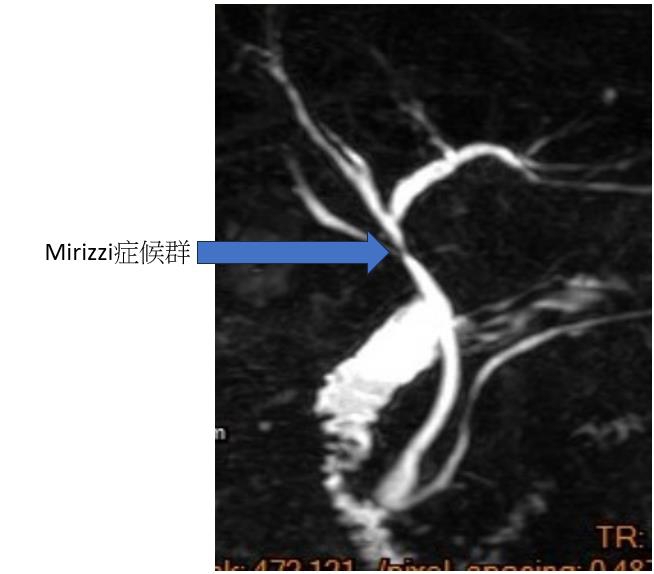

【記者林獻元台中報導】衛生福利部豐原醫院日前收治一名謝姓男士64歲,因腹痛又加上臉色發黃的狀況到醫院就診,外科主任袁天民醫師初步診視後為急性膽囊炎。術前安排核磁共振檢查發現為Mirizzi症候群(為膽結石卡在膽囊管或膽囊頸部)症候群,緊急安排手術,住院5日後已康復出院。

袁天民表示,Mirizzi症候群主要發生在膽管與膽囊的接口處,因膽囊頸部的結石壓迫膽管,造成整個膽管跟膽囊管的結構無法清楚被看見,若採用傳統腹腔鏡膽囊切除手術,可能在手術中造成對膽管的損傷。